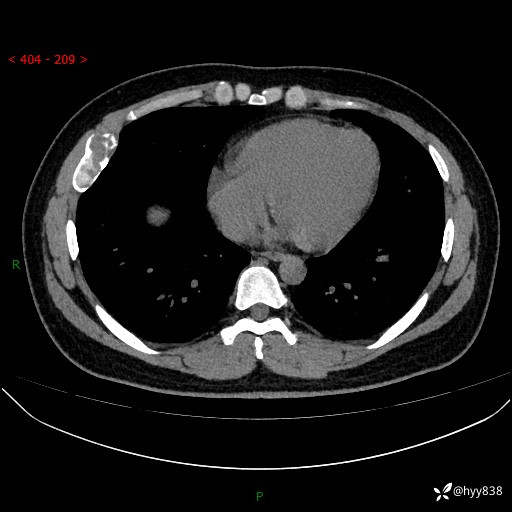

年轻小伙,右侧胸部疼痛4天余。病理科说肯定不是骨纤,那是啥---结果公布~

年龄:24岁

主诉:右侧胸部疼痛4天余。

现病史:患者约4天前突发右侧胸部疼痛,无瘙痒,无头痛、头晕,无心慌、胸闷、呼吸困难、咳嗽、咳痰、咯血,无腹痛、腹胀等不适,未作进一步诊治。于2024年5月外院行胸部CT平扫示右侧肋骨骨质改变。现为求进一步治疗,遂于我院就诊。门诊以“胸壁肿物”收入我科。 患者自起病以来,精神可,睡眠可,饮食可,大小便正常,体重无明显改变。

胸部CT平扫